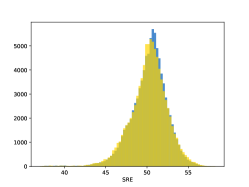

To visualise similarity metrics that compare image pairs (RMSE, SRE, SSIM) two metric distributions are generated: intra-similarity and inter-similarity. For each compared sample 300 random images are selected. The inter-similarity distribution is calculated for each image pair combination from both compared samples e.g. generated images of COVID-19 and real images of COVID-19. For the intra-similarity, all pairs of images in a single sample e.g real images of COVID-19 are considered. By comparing the shape of intra-similarity for the training subsample (Dataset) with the inter-similarity of training and generated samples the quality of the generated sample can be judged. It is also possible to compare in this way between the four image classes present in the dataset. The resulting distributions of inter-similarity of COVID-19 and the three remaining classes are compared in Fig. 4 to distributions of intra-similarity of the COVID-19 sample for each metric. All metrics, as expected based on available medical evidence Rubin et al. (2020), indicate that there are visible differences not only between COVID-19 and normal samples but also between viral pneumonia and lung opacity. Therefore, all classes should be distinguishable.

To visualise differences between synthetic and real samples distributions are generated for each of the RMSE, SRE and SSIM metrics: intra-similarity and inter-similarity. For each compared sample 300 random images are selected. The inter-similarity distribution is calculated for each image pair combination from both compared samples e.g. generated images of COVID-19 and real images of COVID-19. For the intra-similarity, all pairs of images in a single sample e.g real images of COVID-19 are considered. The distributions for generated samples describe very well the distributions for corresponding real images as shown in Fig. 6.

The quality of generated images is also confirmed with classical similarity metrics. The distributions of those similarity measures between generated and real images are compared for each sample with the distribution obtained within the real samples 6. The distributions for generated samples describe very well the distributions for corresponding real images. For an example see the results for the SSIM metric presented in Fig. 10. The small visible differences are almost insignificant compared to differences observed between the classes in Fig. 4.